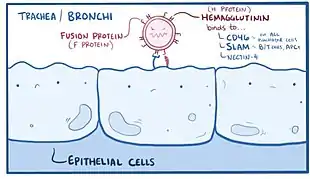

Once the measles virus gets onto the mucosa, it infects the epithelial cells in the trachea or bronchi.[56][57] Measles virus uses a protein on its surface called hemagglutinin (H protein), to bind to a target receptor on the host cell, which could be CD46, which is expressed on all nucleated human cells, CD150, aka signaling lymphocyte activation molecule or SLAM, which is found on immune cells like B or T cells, and antigen-presenting cells, or nectin-4, a cellular adhesion molecule.[56][58] Once bound, the fusion, or F protein helps the virus fuse with the membrane and ultimately get inside the cell.[56]